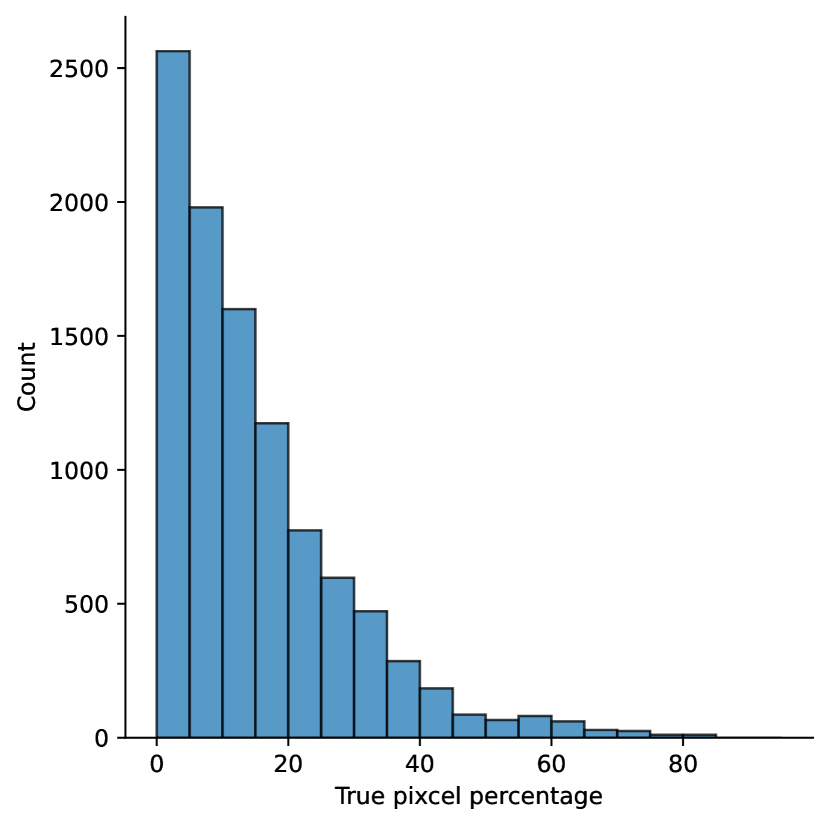

A few sample images and the corresponding masks of the polyp dataset in HyperKvasir are shown in Fig 2. The polyp images are RGB images. The masks of the polyp images are single-channel images with white () for true pixels, which represent polyp regions, and black () for false pixels, which represent clean colon or background regions. In this dataset, there are different sizes of polyps. The distribution of polyp sizes as a percentage of the full image size is presented in the histogram plot in Fig 3, and we can observe that there are more relatively small polyps compared to larger polyps. Additionally, a subset of this dataset was used to prove that the performance of segmentation models trained with small datasets can be improved using our SinGAN-Seg pipeline, and the whole dataset was used to show the effect of using SinGAN-Seg generated synthetic images instead of a large dataset which has enough data to train segmentation models. In this regard, this dataset was used for two purposes:

To understand the difference between the mask distribution of real images and synthetic images, we plotted pixel distribution of masks of synthetic images in Fig 6. This plot is comparable to the pixel distribution presented in Fig 3. The randomness of the generations made differences in the distribution of true pixel percentages compared to the true pixel distribution of real masks of real images. However, the overall shape of synthetic data mask distribution shows a more or less similar distribution pattern to the real true pixel percentage distribution.